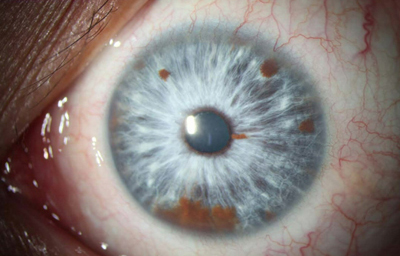

Síndrome de Waardenburg (Bilateral) PAX3 (Neurocristopatia) (22,23)Es un grupo con unas condiciones genéticas raras por lo general de herencia autosomica dominante, es una forma de albinismo irregular, fluctuante; tienen epitelio pigmentario normal y visión normal; sinembargo en el tipo II y IV hay también herencia autosomica recesiva.- Se describen 4 tipos en este síndrome.

El tipo 1 se caracteriza por Telecanto, cierto grado de Hipoacusia congénita y deficiencias pigmentarias en piel con manchas blancas, Mechon blanco en el pelo y deficiente pigmentación del Iris bilateral. Mutación del PAX3

OD

Archivo fotográfico Dr. Francisco Barraquer.

OI

Archivo fotográfico Dr. Francisco Barraquer.